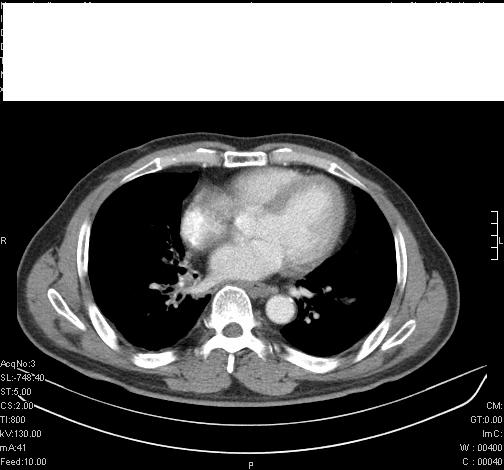

标题: CT6685:右肺阻塞性炎症,增强CT。

前几天,发了患者的平扫片,患者抗炎一周后增强扫描。右中叶病灶吸收明显,但下叶病灶未见明显吸收。右肺门可见结节影,看来凶多吉少

右肺下叶支气管管腔狭窄,管壁增厚,右下肺见斑片状高密度影,考虑右侧肺门中心肺癌伴阻塞性肺炎

右肺下叶散在的斑片状致密影,下叶支气管变窄。考虑:右肺慢性炎症。

右肺下叶支气管壁不规则增厚,右肺下叶有斑片状影分布。考虑右肺中央型肺癌伴右肺下叶阻塞性改变。建议支纤镜检查。平扫比增强较好显示了病变情况。

右主支气管狭窄,管壁增厚。考虑右中心性肺ca伴阻塞性肺炎。

既然抗炎治疗有效,可继续治疗;右肺下叶支气管管腔狭窄,管壁增厚,右下肺见斑片状高密度影,右侧主支气管后见结节影(淋巴结?),肺癌不能排出。